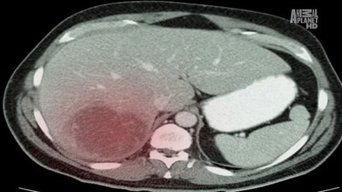

A schoolteacher deals with an amoeba that eats at his liver and causes him high fever, abdominal pain, sweating, and chills. A young dancer gets worms from eating contaminated pork in her muscle tissue, causing her to get hives all over her body and her limbs to become stiff and painful. A retiree gets scabies from mites he got from staying in the hospital in the past.